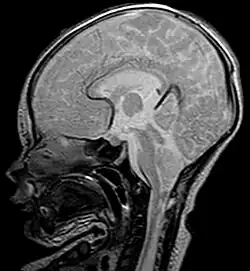

K diagnostice se dnes nejčastěji užívá MRI, dále 3D či jednoduché CT.

Arnoldova–Chiariho malformace (dnes častěji označována pouze jako Chiariho malformace) je nejběžnější vrozený strukturální defekt mozečku s výskytem 1 na 1000 porodů, častěji postihující ženy než muže. Tento syndrom popsal jako první v 19. století rakouský patolog Hans von Chiari. Obecně jde o defekt s dislokací větší či menší části mozečku a prodloužené míchy do foramen magnum (velký týlní otvor) a páteřního kanálu horní krční etáže. Podle rozsahu, příčin a přidružených komplikací dělíme CM na čtyři typy.

Typ I: Spočívá v herniaci tonsil mozečku ve foramen magnum, obvykle bez zapojení mozkového kmene. Tento typ je nejčastější formou a obvykle je asymptomatický, na vadu se často přijde v pokročilém věku náhodně při diagnostice jiných poruch, pokud vůbec. V některých případech se projevují bolesti hlavy a mozečkový syndrom v závislosti na míře dislokace, která je obvykle větší než 5 mm, ale může dosahovat i 15 až 20 mm.